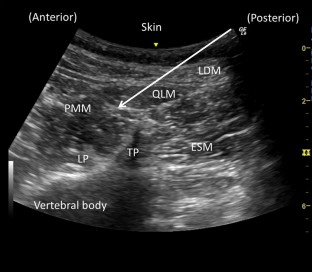

Fig. 1